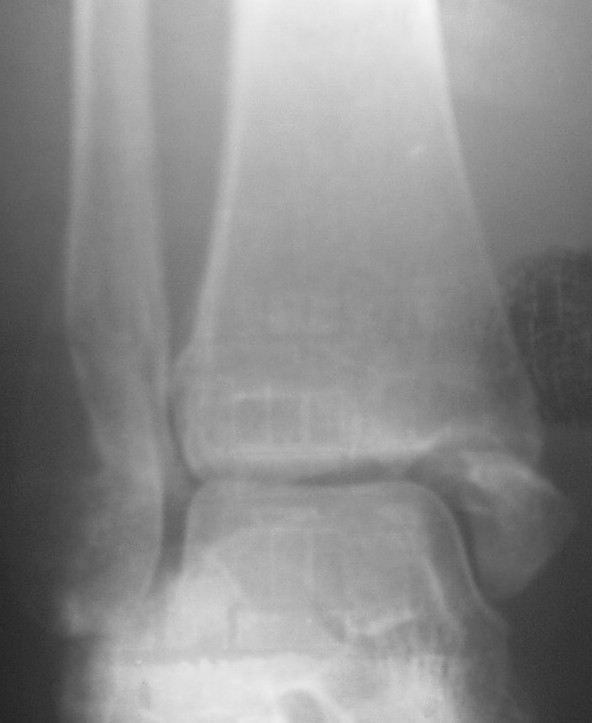

Трехчетвертной контрлатеральный

На боковом довольно неплохой сустав, скудная информация о положении вилки сустава при косой рентгенограмме (Mortise view) из-за положения стопы во внутренней ротации и эквинуса во время ренгенограммы.

"Деформирующие краевые костные разрастания по внутренней замыкательной пластине мало-, большеберцовой и таранной костей"

Мне кажется это тень внутренней лодыжки, которая находится в положении сгибания (flexion), т.е. указывающее на неправильно сросшийся или несросшийся перелом.

На прямом снимке наружная лодыжка немного укорочена и по описанию на КТ синдесмоз расширен.

На представленных снимках с исправлением, нейтральное положение стопы во время рентгенограммы, укорочение малоберцовой не менее 4-5 мм и ротация, смещенная и ротированная внутренняя лодыжка.

Рекомендуемая реконструкция: удлинение малоберцовой с исправлением ротации, исправление внутренней лодыжки с фиксацией и фиксация синдесмоза через пластины, по моему уменьшат болевой синдром у этой больной.